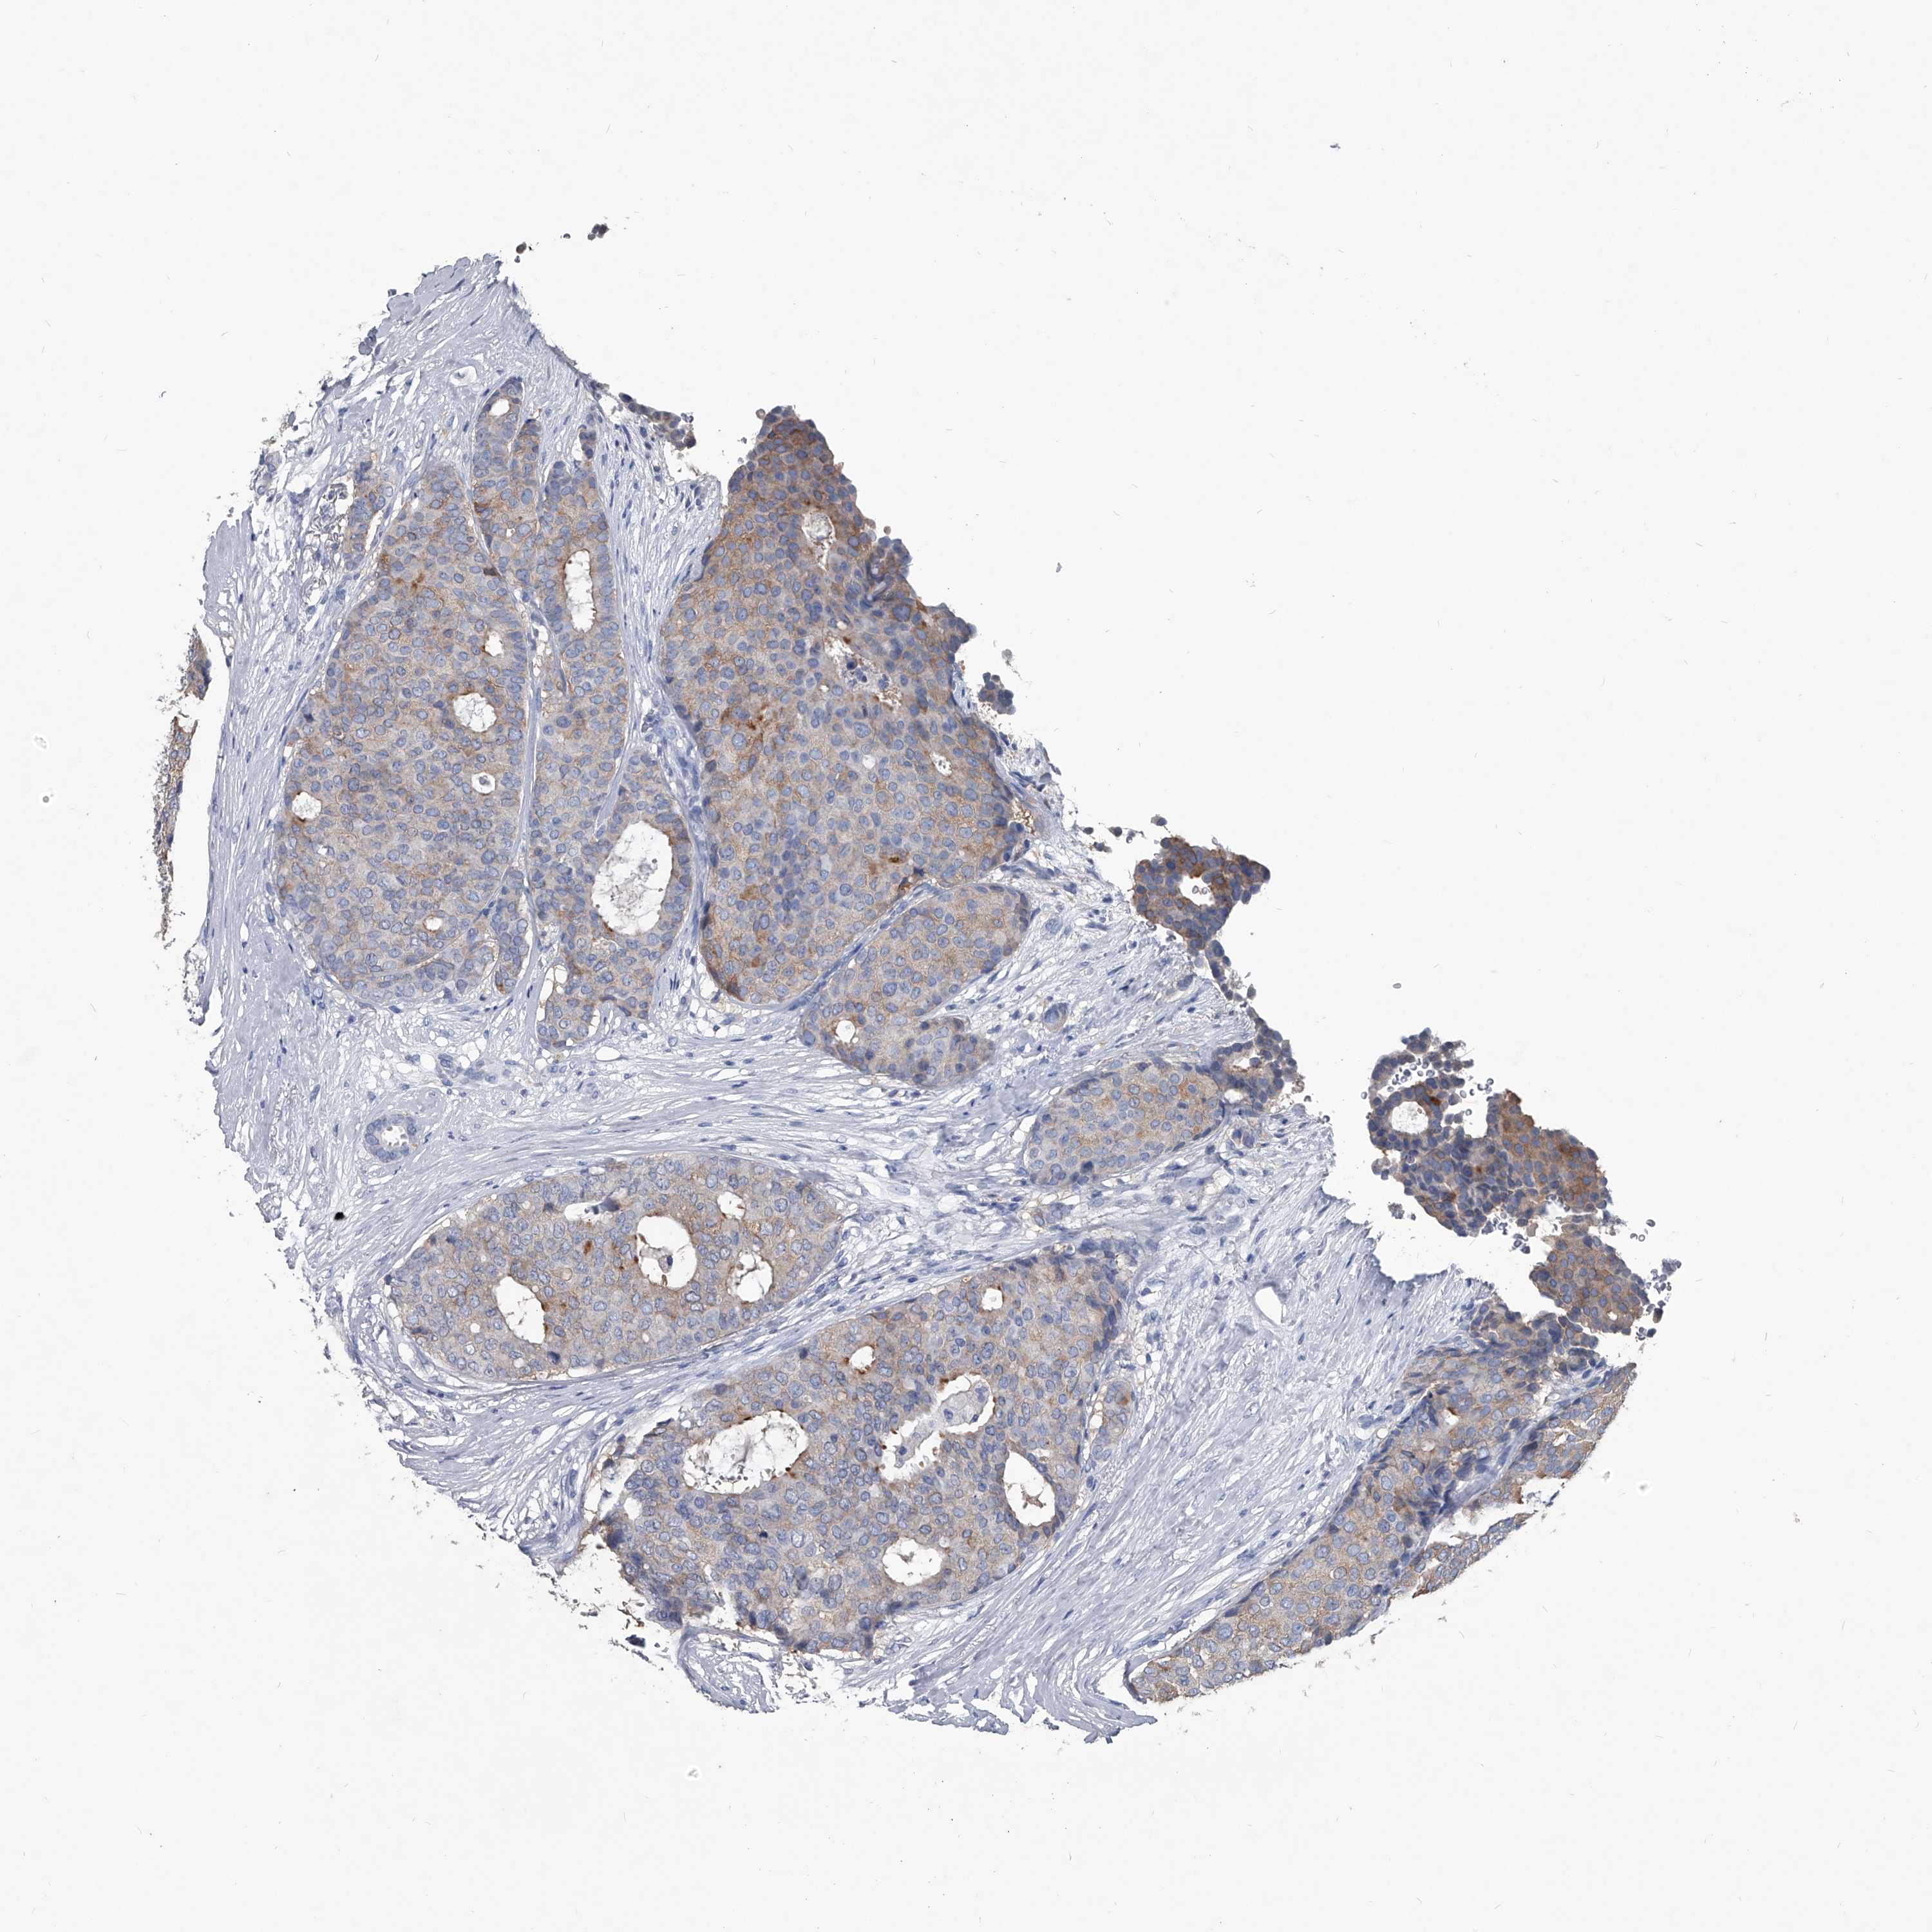

CANCER BREAST CANCER Show tissue menu

BRCA TCGA BRCA VALIDATION PROTEIN EXPRESSION